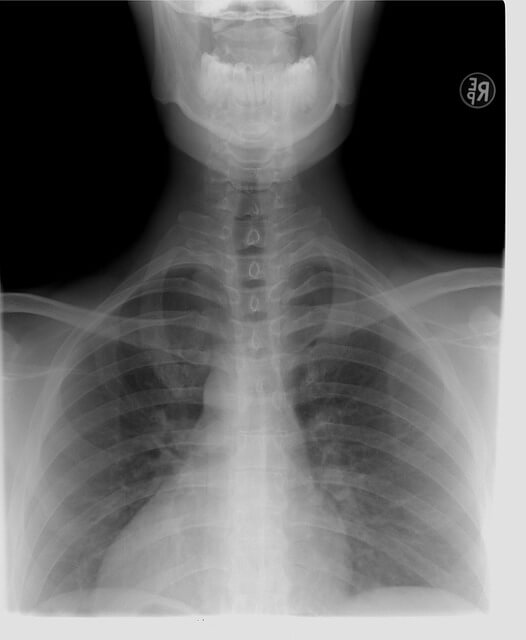

첫째, 엑스레이를 촬영해 흉부에 염증이 있는지 확인합니다.